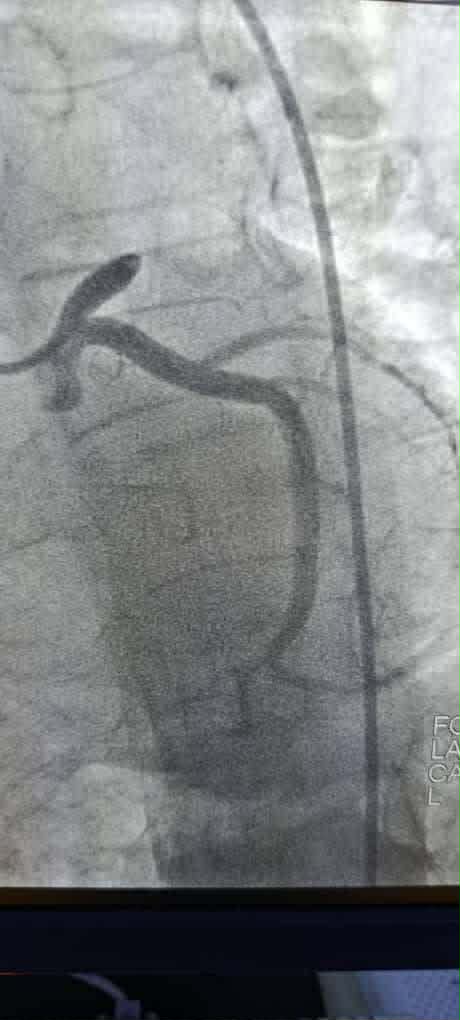

الأولى: مريض في الأربعينات يعاني من احتشاء سفلي مع حصار قلب تام وصدمة قلبية. تم فتح الشريان المنعكس المسدود تمامًا، مما أدى إلى تراجع حصار القلب مع تحسن في الحالة الهيموديناميكية واستقرار الحالة العامة.

الثانية: مريض في الأربعينات راجع بخناق صدر شديد، مع تاريخ عائلي حافل بالأزمات القلبية والوفيات القلبية. تم فتح الشريان الهامشي المسدود تمامًا باستخدام تقنية “Kissing stent” على تفرع الشريان المنعكس الأساسي، تلاها تحسن ملحوظ في الحالة العامة واستقرار الألم الصدري.